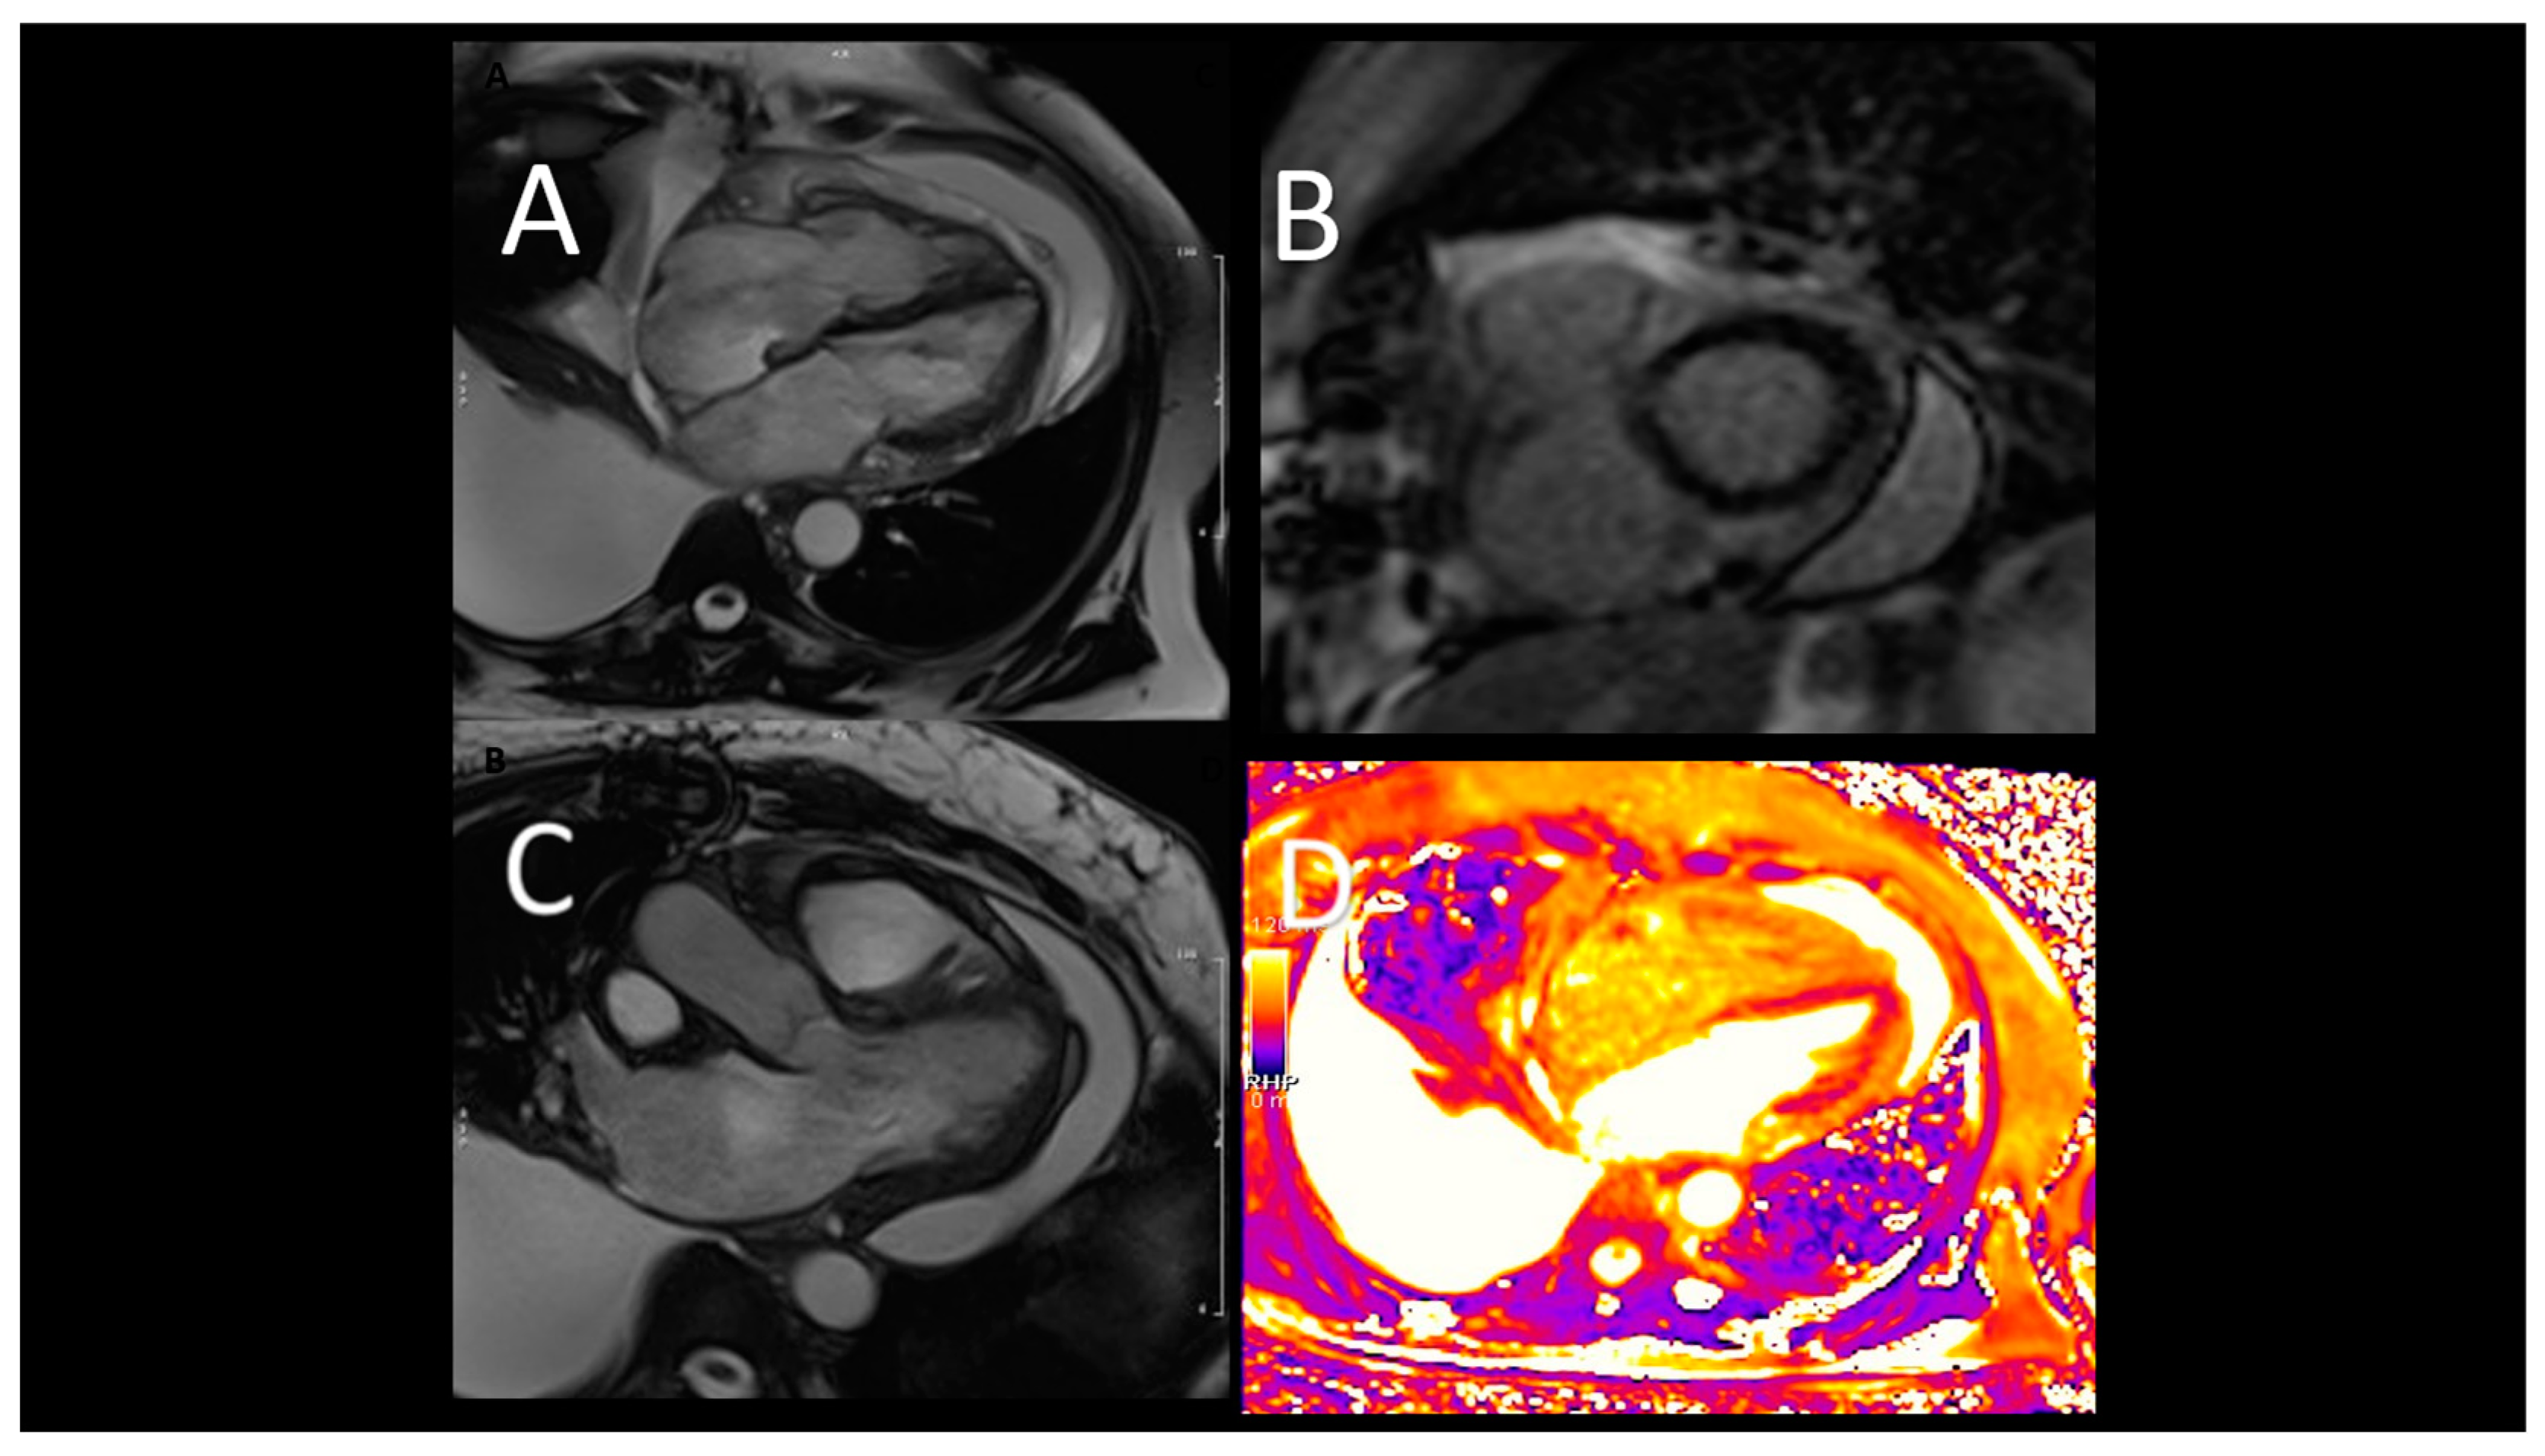

As for IABP, Impella devices are commonly placed under fluoroscopic guidance, but in patients with refractory shock, preventing transportation of the patient to the cardiac catheterization laboratory, TEE can help bedside positioning of the device (32). One single centre study demonstrated no difference in Impella-related complications when comparing TEE alone guided placement with the fluoroscopic guided cohort (33). The mid-esophageal long-axis and 4-chamber views can be used to visualize the guidewire crossing the aortic valve. The catheter should be oriented towards the ventricular apex. TEE can also confirm the absence of iatrogenic aortic dissection from the procedure (32). Both TTE and TEE are helpful in identifying correct positioning of the Impella device (Figure 2).

The distance from the aortic valve to the Impella inlet should be 3.5-5 cm, while the Impella outlet should be 1.5-2 cm above the sinuses of Valsalva (32). Color flow Doppler shows a mosaic pattern at the Impella inlet and outlet confirming further its proper position. To note, the Impella devices can migrate: in this case the mosaic pattern will be visualized on the same side of the aortic valve (32). Three-dimensional echocardiography can help visualization of Impella positioning in comparison to other anatomical structures (34). After placement, additional complication of the Impella placement such as damage to the mitral or aortic valve, pericardial effusion, and rupture of LV free wall must be excluded. The ideal position of the septum is median during the diastole, and displacements may indicate the presence of a right dysfunction or the need to change the speed of the Impella device. Finally, echocardiographic data can be used in conjunction with haemodynamic ones to guide the weaning of the Impella by evaluating the response of the LV to progressive reduction in the support provided by the Impella (the P level). CCT plays an important role in confirming endoventricular thrombi before Impella implantation (35). We know that the most common complications after Impella placement are hemolysis, vascular complications, bleeding, and limb ischemia. CCT scan can identify complications such as damage to the mitral and aortic valve systems and positioning of the device. CMR is not indicated in monitoring after Impella implantation (see Table 3).

Figure 2. Transthoracic echocardiographic evaluation after Impella implantation A) correct device's position; B) uncorrect position (towards the LV apex), C) CCT showing incorrect, apical position.